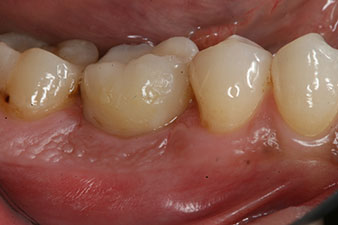

The final pictures show the screw-retained monolithic composite crown in place and the x-ray check (Fig. 9 and 10) (6).

composite crown

Fig. 9: The final composite crown was cemented on a PEEK hybrid abutment in the laboratory and can be screwed in place immediately.